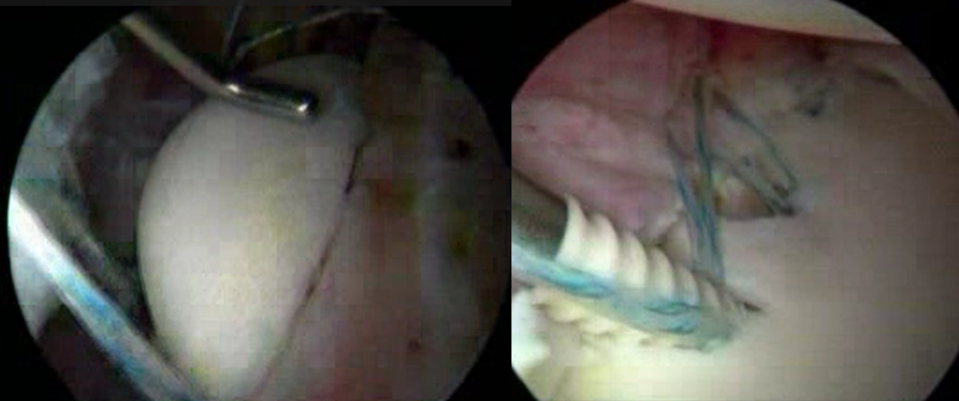

腱板断裂においては、鏡視下手術を中心に行っております。腱板断裂は、転倒などの外傷性のものと、日常の負荷、動作時のすり減りなどで変性し断裂するものがあります。腱板断裂部の断裂サイズの大きい大・広範囲断裂といわれる症例においては、腱断端部の緊張を抑えて修復する、Debeyre-patte変法(筋前進術)などを行っております。

- 反復性肩関節脱臼に対しては、スポーツ内容や仕事内容などによって方針を検討し、関節窩や上腕骨の骨欠損が大きいもの、コンタクトスポーツなどの再脱臼リスクの高い症例に関しては、関節窩の骨欠損部を補填するため、人工骨を用いて鏡視下Bankart修復術を施行し、再脱臼率の低減を目指しています。